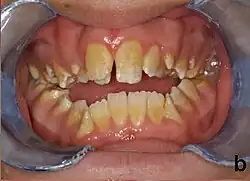

People with amelogenesis imperfecta may have teeth with abnormal color: yellow, brown or grey; this disorder can affect any number of teeth of both dentitions. Enamel hypoplasia manifests in a variety of ways depending on the type of AI an individual has (see below), with pitting and plane-form defects common.[4] The teeth have a higher risk for dental cavities and are hypersensitive to temperature changes as well as rapid attrition, excessive calculus deposition, and gingival hyperplasia.[5] The earliest known case of AI is in an extinct hominid species called Paranthropus robustus, with over a third of individuals displaying this condition.[6]

AI can be classified according to their clinical appearances:[19]

- Type 1 - Hypoplastic

- Enamel of abnormal thickness due to malfunction in enamel matrix formation. Enamel is very thin but hard & translucent, and may have random pits & grooves. Condition is of autosomal dominant, autosomal recessive, or x-linked pattern. Enamel differs in appearance from dentine radiographically as normal functional enamel.[20]

- Type 2 - Hypomaturation

- Enamel has sound thickness, with a pitted appearance. It is less hard compared to normal enamel, and are prone to rapid wear, although not as intense as Type 3 AI. Condition is of autosomal dominant, autosomal recessive, or x-linked pattern. Enamel appears to be comparable to dentine in its radiodensity on radiographs.

- Type 3 - Hypocalcified

- Enamel defect due to malfunction of enamel calcification, therefore enamel is of normal thickness but is extremely brittle, with an opaque/chalky presentation. Teeth are prone to staining and rapid wear, exposing dentine. Condition is of autosomal dominant and autosomal recessive pattern. Enamel appears less radioopaque compared to dentine on radiographs.

- Type 4 - Hypomature hypoplastic enamel with taurodontism

- Enamel has a variation in appearance, with mixed features from Type 1 and Type 2 AI. All Type 4 AI has taurodontism in common. Condition is of autosomal dominant pattern. Other common features may include an anterior open bite,[21] taurodontism, sensitivity of teeth.

Preventive and restorative dental care is very important as well as considerations for esthetic issues since the crown are yellow from exposure of dentin due to enamel loss.[5] The main objectives of treatment is pain relief, preserving patient's remaining dentition, and to treat and preserve the patient's occlusal vertical height.[20]